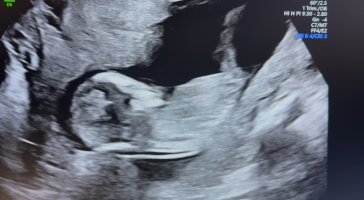

Veldig utydelig NUB, men tipper guttVis vedlegget 474235

TIpper guttVis vedlegget 474235